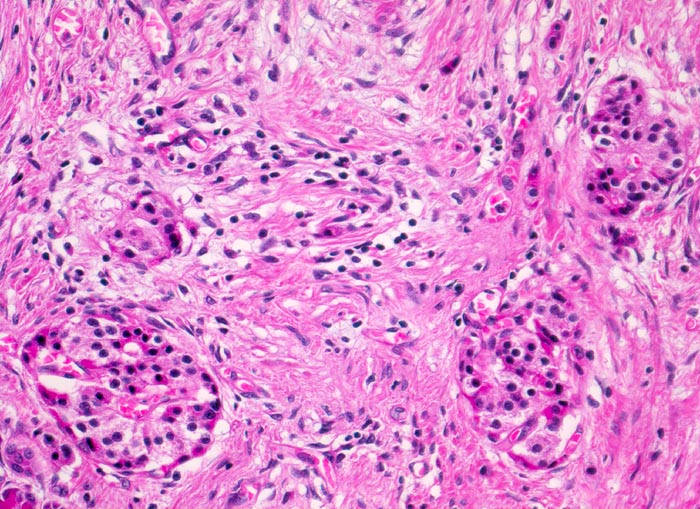

Je nach Ursache der chronischen Pankreatitis unterscheidet sich das Muster der Fibrose. Die Nekrosen des interlobulären Gewebes und der interlobulären Gänge bei ethylischen Pankreatitisschüben führen primär zu einer interlobulären Fibrose und interlobulären Gangstrikturen. In den betroffenen interlobulären Gängen führt der Sekretstau zur Konkrementbildung (verkalkte Proteinpräzipitate). Wie bei einer chronisch obstruktiven Pankreatitis kommt es in den unvollständig drainierten Läppchen zu einer Atrophie der Azini verbunden mit intralobulärer Fibrose. Letztere Areale enthalten schliesslich nur noch Reste unregelmässig verteilter Gänge, Inseln, Nerven und Gefässe. In vielen Fällen lassen sich extrapankreatische Pseudozysten gefüllt mit nekrotisch-hämorrhagischem Detritus in der Nachbarschaft der fibrosierten Bezirke nachweisen. Ein Tumor (> 2066), eine Narbe oder einen Stein können als Folge einer Obstruktion des Pankreasganges im Pankreaskopf eine diffuse Atrophie und Fibrose des Pankreas nach sich ziehen. Diese Form wird als chronische obstruktive Pankreatitis bezeichnet und ist gekennzeichnet durch eine deutliche poststenotische Dilatation des betroffenen Pankreasganges ohne Konkrementbildung und eine diffuse Fibrose des an den obstruierten Gang angrenzenden Parenchyms. Bei einer Schädigung des Gangepithels und der Gangwände wie bei hereditärer oder Autoimmunpankreatitis entwickelt sich primär eine periduktale Fibrose. Im Gegensatz zum duktalen Adenokarzinom ist das erhaltene Parenchym bei der chronischen Pankreatitis lobulär angeordnet. Drüsenepithelien zeigen keine Atypien. Karzinomverdächtig sind irregulär infiltrierende atypische Drüsen, atypische Drüsen in unmittelbarer Nachbarschaft von grösseren Gefässen ohne dazwischenliegende Azini, Perineuralscheideninvasion, rupturierte oder inkomplette Drüsen, und Drüsen mit luminalem nekrotischem Detritus.

• Erhaltene Läppchenarchitektur.

• Breite Bänder von sklerosiertem zellarmem Bindegewebe verlaufen zwischen den Läppchen.

• Atrophie des exokrinen Pankreas.

• Erhaltene Inseln und Gangstrukturen.

• Spärliches chronisches Entzündungsinfiltrat.